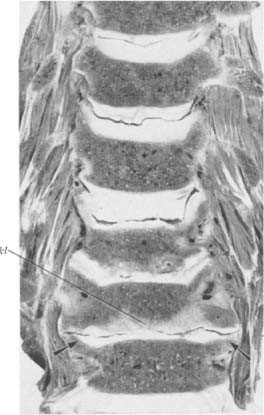

Halswirbelsäule eines 89jährigen Mannes. Obere drei Bandscheiben gut erhalten. Bei der vierten Bandscheibe erkennen wir die schräg nach außen gekippten Processus uncinati, die infolge der hohen statischen Beanspruchung samt ihrem Gegenpol in symmetrischer Weise stark sklerosiert sind (Pfeile). Die Wirbelkörperendplatten sind sonst frei von Sklerosierung